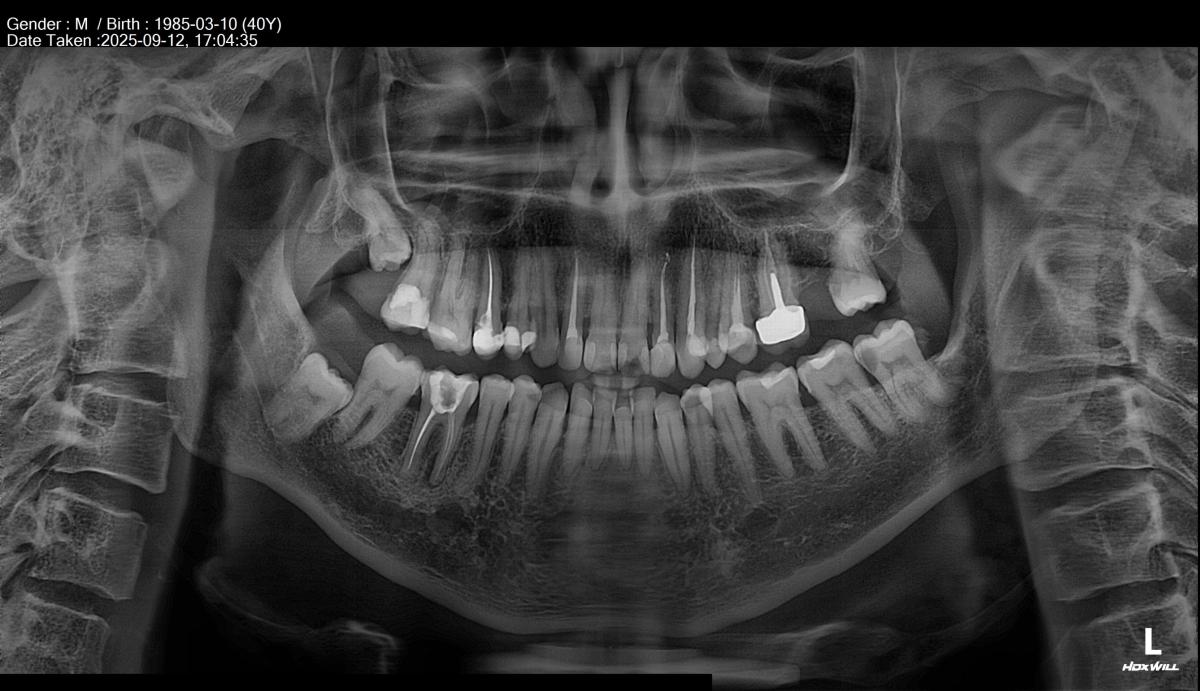

Ортопантограмма сделана неделю назад (12 сентября 2025 года).

Прикладываю также прицельный снимок 46 зуба (в центре на центральном снимке) и 25 зуба (верхний левый второй премоляр, на прицельном снимке крайний слева) 7-месячной давности (27 февраля 2025 года).

Беспокоит 46 зуб (нижний моляр справа). Лет 15-20 назад запломбировали каналы.

Я проконсультировался у 2 разных докторов очно. Но так и не пришел к единому заключению. Я только понял, что есть апикальная инфекция у корня 46 зуба из-за прошлого некачественного лечения каналов.

- У каких зубов (номера) есть убыль костной ткани и на сколько (%, мм)?

- Есть ли пародонтит?

- Есть ли поддесневой камень и пародонтальные карманы?

- Надо ли делать deep clean (или кюрретаж)?

- На 38 зубе врач обнаружил кариес. Надо ли его удалять или можно пока наблюдать?

- На 25 зубе (верхний левый второй премоляр) надо ли перелечивать каналы или просто поставить пломбу?

- Есть ли еще какие-то проблемы?